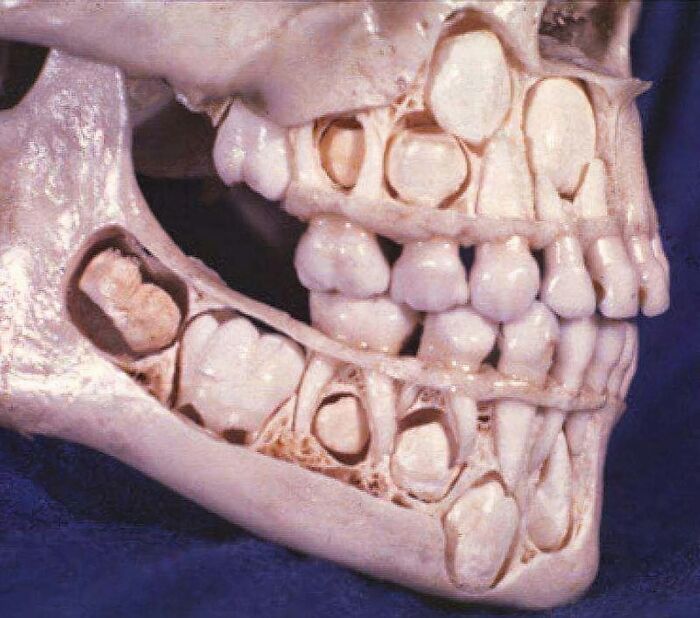

A child's skull before losing baby teeth